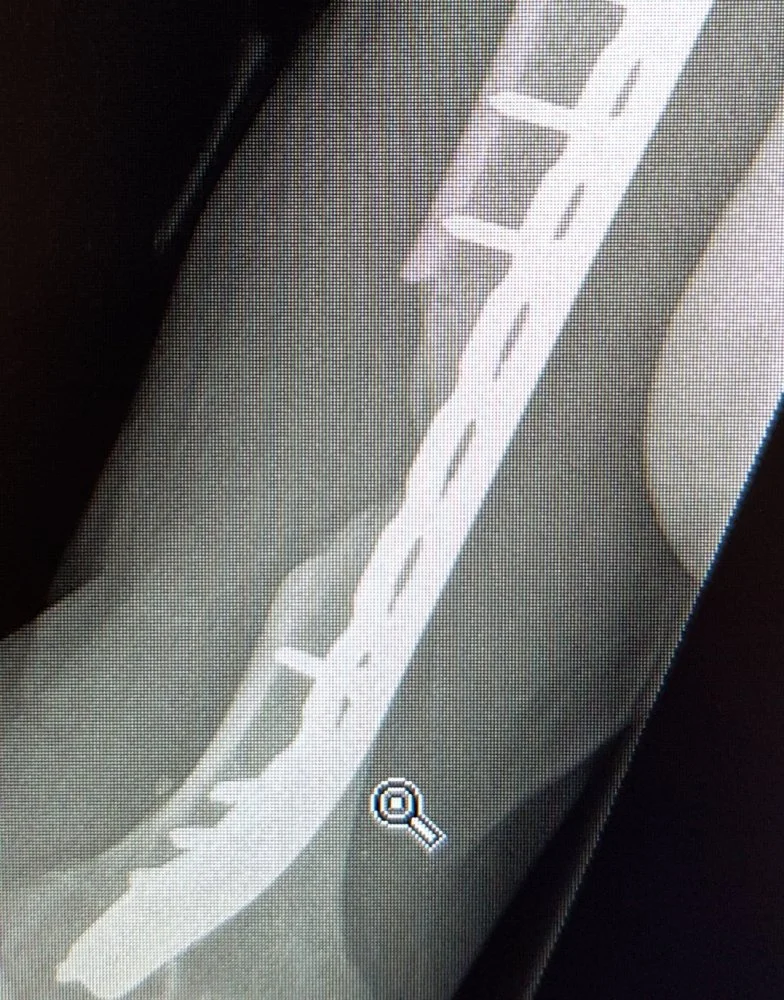

No karseeta ja karseeta, jos ei ny ihan jauhelihaksi menneestä puhuta, niin yleensä jos 10 sentin matkalla luuta on yli puolen kymmentä palaa niin alkaa tympimään.

Esim olkaluu ennen ja 3kk luusiirteen jälkeen.

Myös näitä viritelmiä ja mömmöjä on ja ne on ihan paskoja. Mutta väliaikaisina ratkaisuna esim tuossa olkaluussa.

Luusementtiä, joka on ehkä kumminkin enemmän sukua pikaliimalle...anteeksi, pleksiä..vai mitä lie, jotain polymetyyliakrylaattia.

Tietenkin jos luu on vain silppua, niin saa se yleensä sinne jäädä ja fiksataan vaan siitä ylitte, kyllä se siihen luutuu.

Mutta joo, riippuu luusta, missä kohti ja mitä luuta ja puuttuuko sitä vai onko silppua...ja onko avomurtuma tai eij.